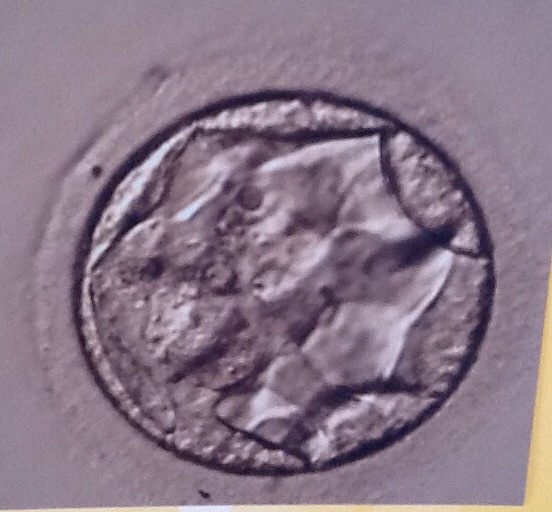

An Tag PU+5 9 Uhr: Transfer von zwei Blastocysten (1x expandiert (Foto) und einmal nicht ganz so weit)

Die Qualität der BC würde ich nach dem Bild mit 2BB einstufen.